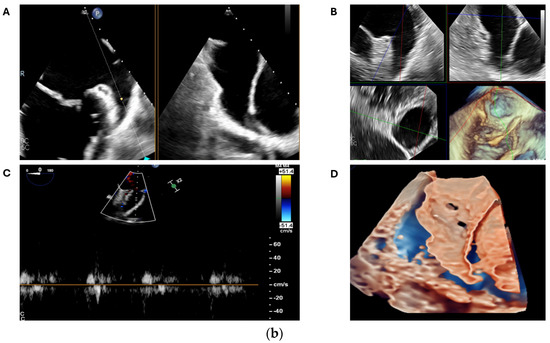

2.2. Transoesophageal Echocardiography

2.2.1. LAA Thrombus Assessment

2.2.2. LAA Measurements (Anatomy and Morphology)

2.2.3. Intra-Procedural TOE